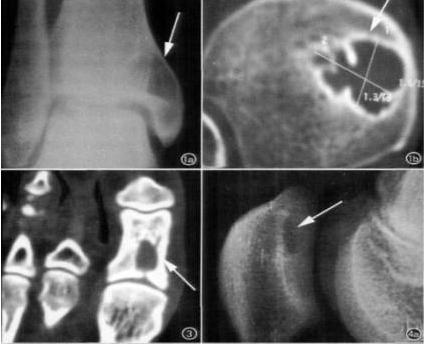

X线:邻近关节面、骨端一侧;囊状骨质破坏,边界清;无骨膜反应及软组织快,有硬化边;骨性关节面完整,关节间隙正常,无退变

MRI:病灶位于关节软骨下,呈囊性,境界清晰,与关节相通;长T1长T2水样信号;长T1短T2纤维组织信号、气体信号;STIR中异常信号均未被抑制。